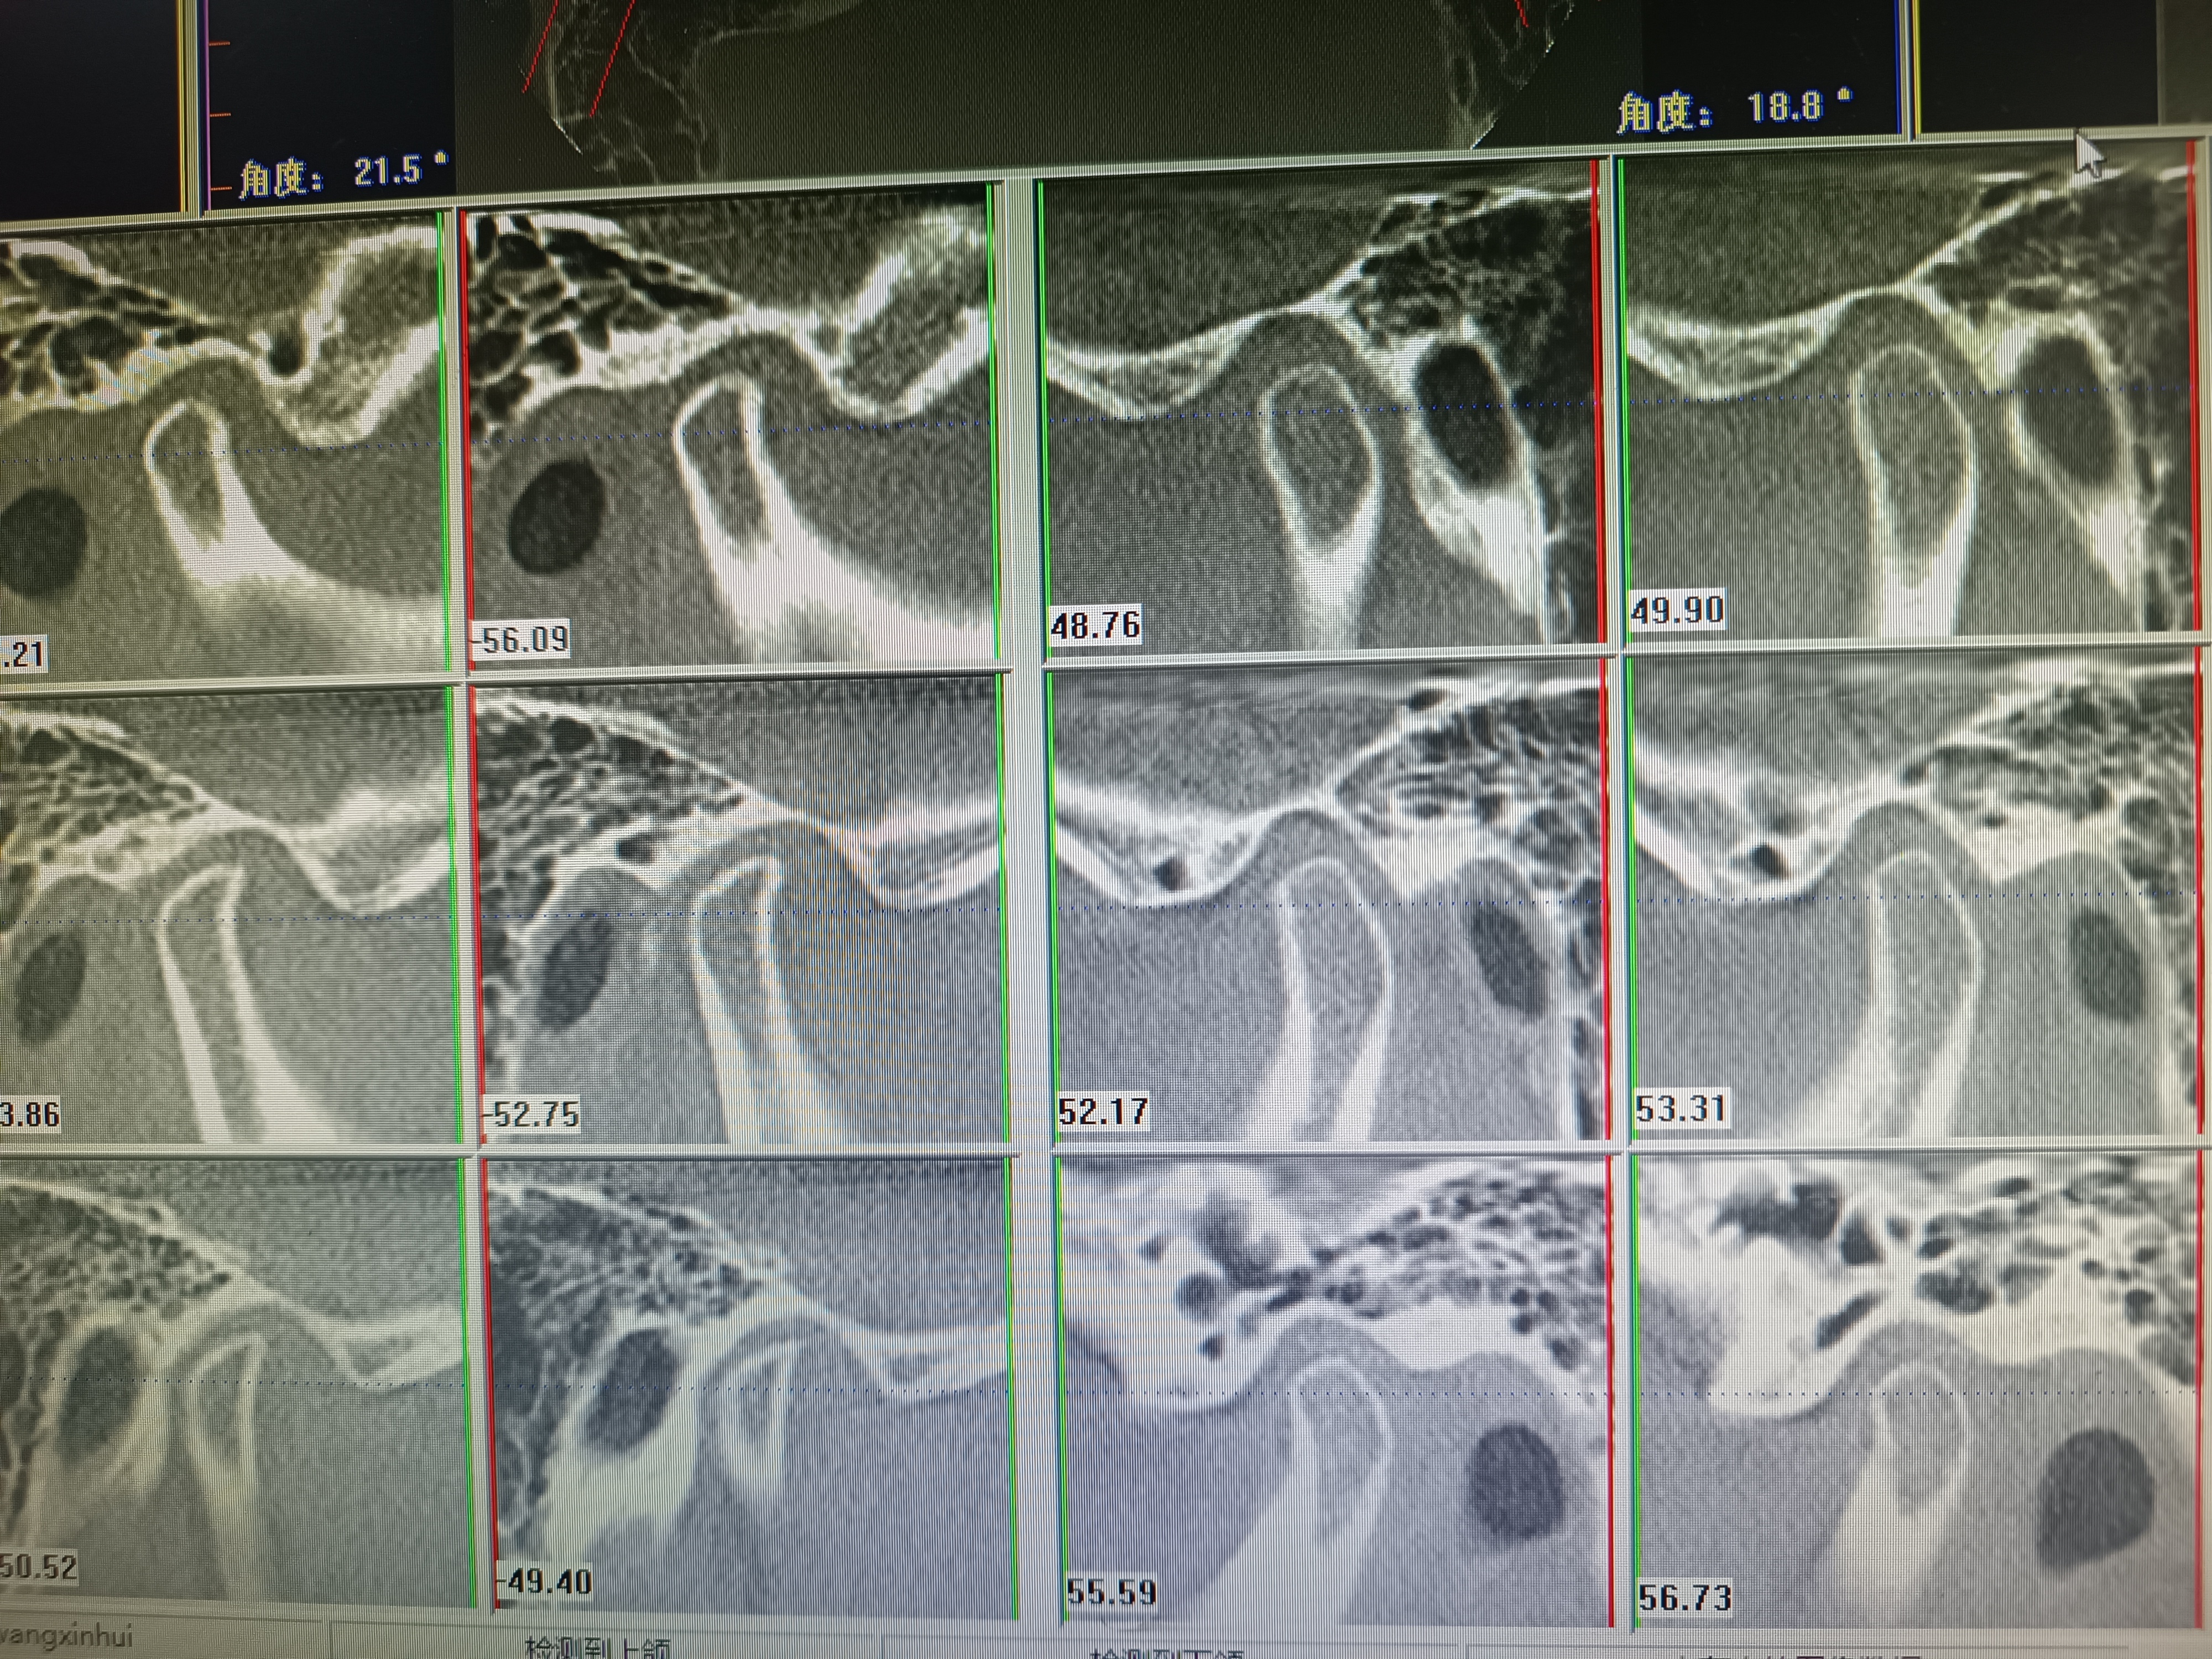

治療前 常規(guī)合墊無法復(fù)位晚期關(guān)節(jié)盤可復(fù)性移位患者。我們利用了新的合墊治療獲得滿意效果,需要患者積極配合。 治療中 左側(cè)晚期關(guān)節(jié)盤可復(fù)性移位側(cè),通過佩戴合墊,關(guān)節(jié)各間隙成功撐開,利于關(guān)節(jié)盤回位。 治療后 治療后1月 患者目前恢復(fù)良好,關(guān)節(jié)盤回位。